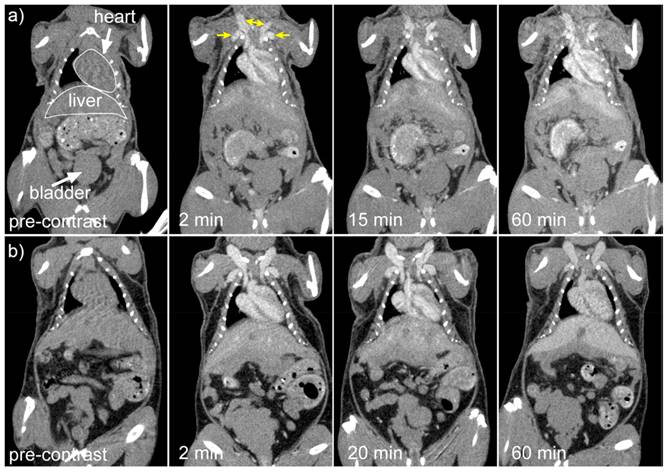

Cruje et al., created an erbium-based contrast agent that satisfies the criteria for micro-CT imaging, which include a stable colloidal structure upon redispersal of high concentrations, the capacity to avoid quick renal clearance, and circulation durations in tiny animals in the tens of minutes. The agent included 100 mg/mL of erbium. To fulfil the needs of live animal micro-CT, contrast enhancement of more than 250 HU was maintained in the blood pool for a maximum of one hour. Mice were scanned using three-dimensional micro-CT before and three times after each contrast agent formulation was administered intravenously. Obtaining each scan took sixteen seconds. In Fig. 5, shows micro-CT pictures that are representative of all the contrast agents. The external jugular and axillary veins, as seen in Fig. 5, were the most prominent after the contrast agent was administered. It seems like the contrast in the heart chambers didn't vary for both formulations for up to 60 minutes. The capacity to differentiate liver from surrounding soft tissue indicated the contrast in the liver as early as the 2-minute time point [136].

Figure 5

Coronal micro-CT pictures depicting the organs and structures of mice that were given a contrast agent formulated at a) 1:1 and b) 0.5:1 PEG114- PLA53:ErNP mass ratios. Reproduced with the permission from ref [136]. Fig. 7 (ACS Publications,2018©).